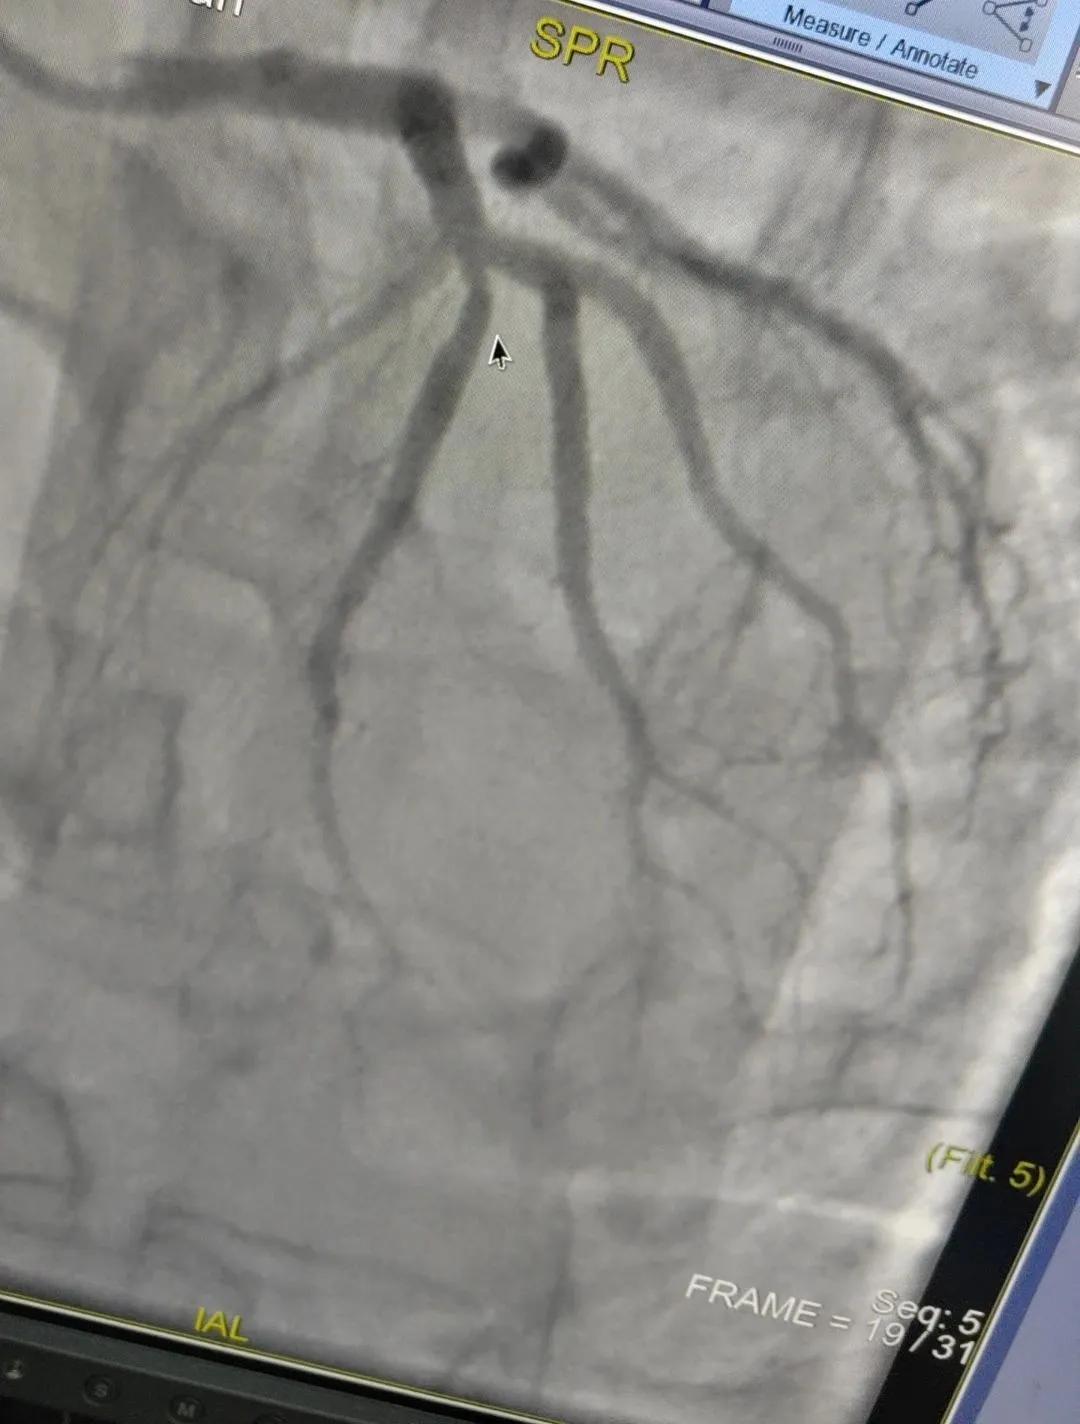

近日,漯河市中醫(yī)院成功開展了一例心腦血管聯(lián)合造影的手術(shù)。

患者男,37歲,兩周前無明顯誘因突發(fā)頭昏,伴右側(cè)肢體無力來院就診,經(jīng)過對患者病情的評估以及心內(nèi)科和腦病科醫(yī)生聯(lián)合會診,需對患者進(jìn)行心腦血管聯(lián)合造影手術(shù)。由神經(jīng)內(nèi)科楊慶堂副主任與心血管內(nèi)科陳云副主任帶領(lǐng)各自的介入團(tuán)隊為該患者順利進(jìn)行了全腦血管造影術(shù)+心血管造影的介入檢查。

術(shù)中心血管造影顯示:LAD中段發(fā)出D1處可見約50%節(jié)段性狹窄,RCA中段狹窄約40%,PLA可見約70%狹窄病變。

腦血管造影顯示:左側(cè)頸內(nèi)動脈嚴(yán)重遷曲,左側(cè)大腦前動脈未顯影,左側(cè)大腦中動脈M1中段以遠(yuǎn)未顯影,M1近段串珠樣嚴(yán)重狹窄,顱底可見少量煙霧血管,后交通動脈未開放;右側(cè)頸內(nèi)動脈嚴(yán)重遷曲。右側(cè)大腦前動脈A1段嚴(yán)重遷曲。

心腦聯(lián)合造影不僅明確患者的病因和病變血管,還為下一步治療提供了有力的依據(jù)。